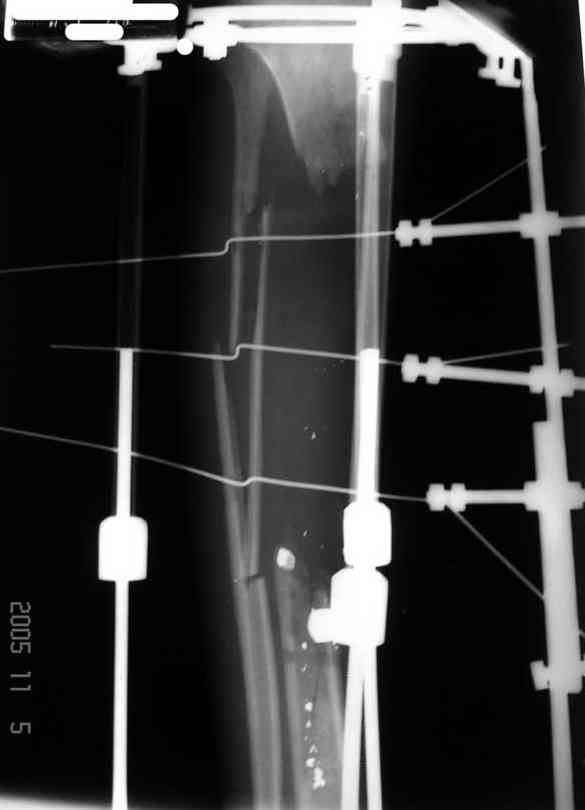

Я думал, что в нижнем отделе голени без мягкотканнего покрытия будет сложно проведения тибиализацию, но твой пример показывает - метод работает даже в таких трудных условиях.

Правда те мои случаи были сделаны давно, еще в Латинской Америке, и конечно качество исполнения отстает от идеалов, но, несмотря на отсутствие нормальных спиц с упором, метод сработал в свое время.